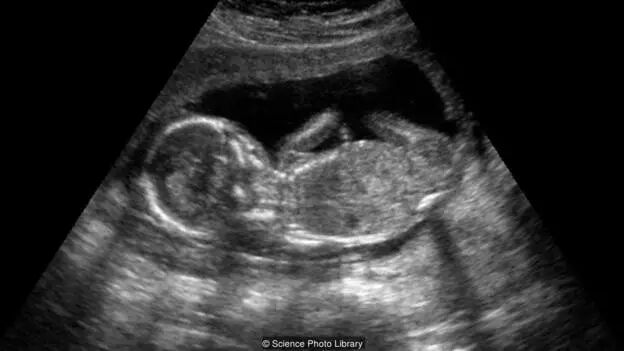

当病人身为孕妇时,情况则变得尤为棘手。在这些案例中,病人的家属得做出令他们心碎的抉择。他们或者接受腹中婴儿的死亡,或当胎儿足够大(一般是24周)时,选择艰巨而令人压抑的医护,直到母亲临产。

在2013年,玛丽兹·蒙诺兹(Marlise Munoz)在得克萨斯周的家中被发现不省人事。医生怀疑病因是肺栓塞的同时,在她腹中发现了14周大的胎儿。两天后,医院宣布她死亡。蒙诺兹曾任护理员,在之前就告诉过她的丈夫,一旦她脑死,她不希望可以自己以人工方式继续存活。她的丈夫申诉,希望院方停止妻子的生命维持系统,但被医院拒绝了。

“心脏跳动的尸体”仍然可能供养一具胚胎成长

”在得克萨斯州,孕妇生前对自己身体的决定会被自动视为无效。如果她希望院方移除自己的生命维持系统,在她死后,这种决定将不会被执行——被强制取消了。她将会被转移到生命维持系统下。”克里斯托弗·博考(Christopher Burkle)说。这位来自明尼苏达州,罗切斯特市的麻醉师与威杰迪克斯以这个主题共著过文章。

这种情况极其罕见,从1982年到2010年仅有30例,但这场在母亲与未出生婴孩利益之间的拔河赛把这个问题抛向我们:在死后,?